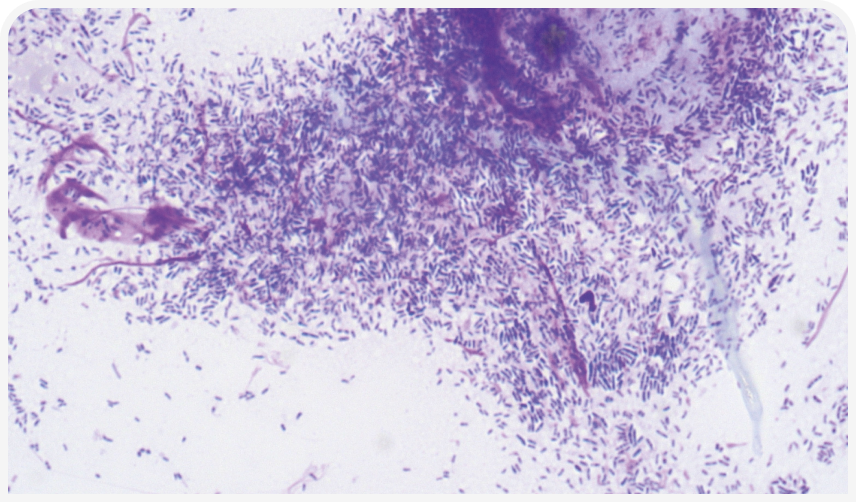

Parnell-Turner H, Griffin CE, Rosenkrantz WS, et al. Evaluation of the use of paired modified Wright’s and periodic acid Schiff stains to identify microbial aggregates on cytological smears of dogs with microbial otitis externa and suspected biofilm. Vet. Dermatol. 2021;32(5):448-e122. DOI:10.1111/vde.13009